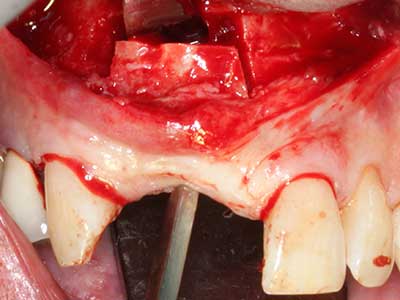

Indication: Preparation near nerves

As noted above, indications for piezosurgery can also be found in the field of conservative dental surgery. Special working tips simplify the exposure of root tips and make it easier to protect nerves and sinus mucous membranes, particularly in the lower premolar and upper posterior tooth regions. Angled diamond tips are used to precisely prepare the resection cavity for the retrograde root filler material for unsealed apical obturation. The ultrasonic technology means the tips can be very slender, which improves the view and the size of the access cavity. As a result, the application of ultrasonic surgery for this indication is one of the standard procedures for apical resection (Del Fabbro, Tsesis et al. 2010, Scarano, Artese et al. 2012).

Indication: Apical resection

When surgical procedures are performed on bone in the immediate vicinity of sensitive structures such as blood vessels or nerves, rotary instruments pose a significant risk of iatrogenic injury. Piezoelectric devices can be helpful for preparation of bone covers and removal of hard tissue close to nerves, particularly for exposure of nerves after iatrogenic injury but also during nerve lateralization for resective and reconstructive procedures or implant placement (Fig. 17-20). Light contact between the piezotip and the nerve does not generally result in damage but proceeding incautiously with saw-like motions or attachments where a residual bone substrate remains may cause temporary or even permanent nerve damage. However, the risk of damage is considered to be substantially lower than when using saws or milling instruments (Pereira, Gealh et al. 2014).